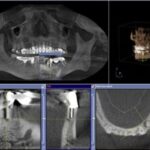

Ein weiterer wichtiger Störfaktor aus dem Zahn-Mund-Kieferbereich können sogenannte Restostitiden sein. Darunter versteht man meist klinisch stumme, lokal symptomfreie Entzündungen von Leerkieferbereichen, häufig als Langzeitfolge von Extraktionen entzündeter Zähne. Diese chronischen Entzündungen sind auf den zweidimensionalen Röntgenbildern kaum zu erkennen. Erst die dreidimensionale Bildgebung (DVT, CT) bringt hier diagnostische Klarheit.

Digitales 2-dimensionales Röntgenbild – Zahn mit Stift ohne Befund

3D-Röntgenbild (DVT) – deutliche sichtbarer ausgeprägter Entzündungsherd an der Wurzelspitze.